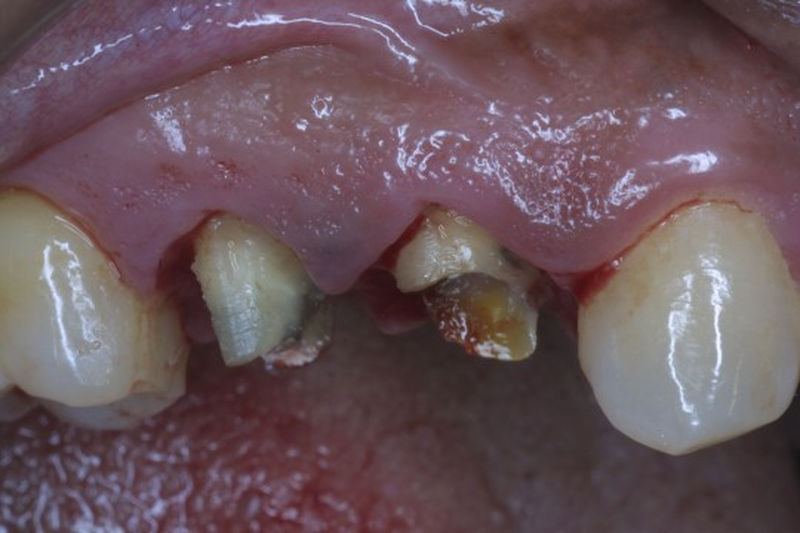

Implante fracasado, extracción, carillas, coronas y prótesis fija.